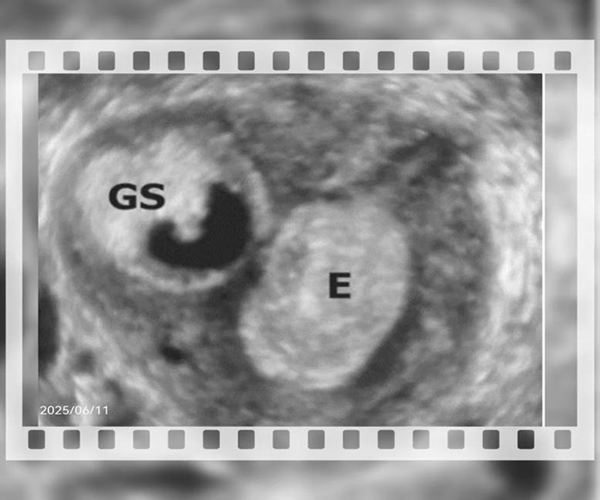

1. 超声检查:首选经阴道超声,若发现孕囊位于子宫肌层内,周围无正常子宫内膜包绕,需高度怀疑。